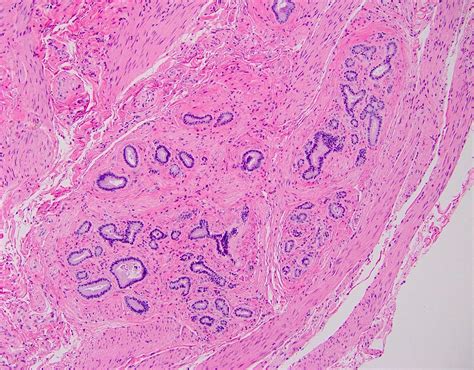

The Duct of Oddi is located at the junction where the common bile duct and the pancreatic duct meet before emptying into the duodenum. This structure is surrounded by the sphincter of Oddi, a muscular valve that controls the flow of bile and pancreatic juices. The sphincter of Oddi relaxes to allow these fluids to enter the duodenum and contracts to prevent backflow.